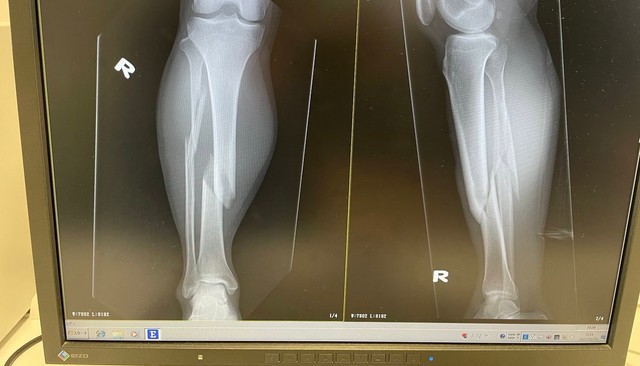

このつぶやきと共に、「合成か?!」と思うほどポッキリと折れた脚の骨のレントゲン写真が投稿されています。これはするさんが電動キックボードに乗って事故を起こし、怪我した時のものだといいます。

「こんな頑健な脚の形してるのにポッキリ折れて…」